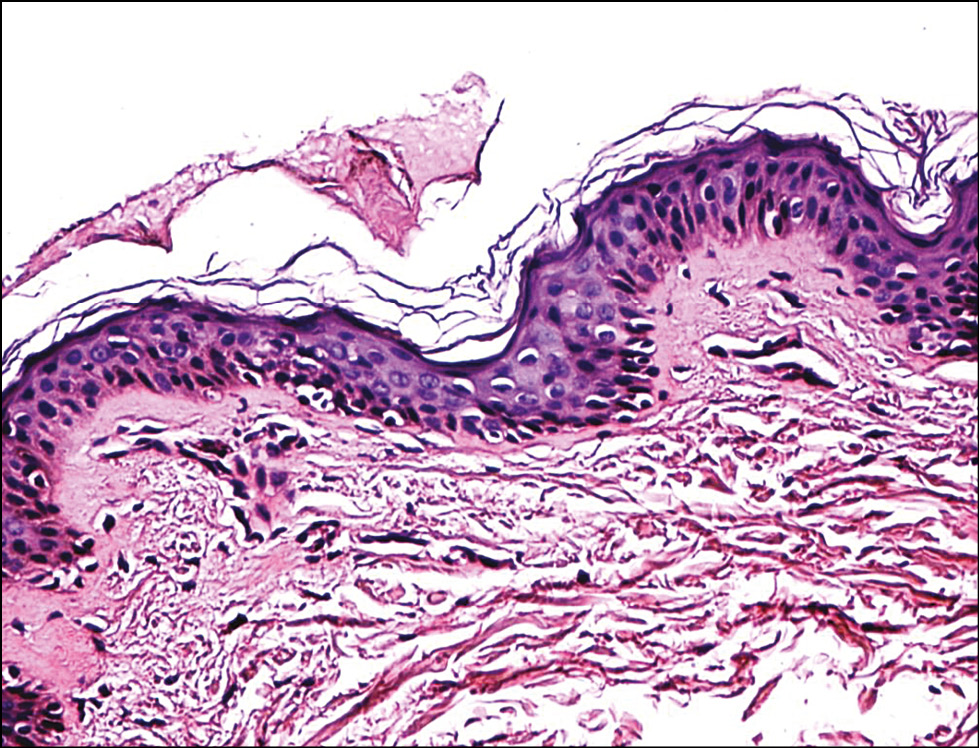

Рис. 1. Гистологическая картина слизистой оболочки полости рта крысы до облучения. Окраска гематоксилином и эозином, х200.

Fig. 1. Histological picture of the oral mucosa of rats before irradiation. Staining with hematoxylin and eosin, x200.

Рис. 2. Гистологическая картина слизистой оболочки полости рта крысы через 30 мин после облучения длиной волны 660 нм. Окраска гематоксилином и эозином, х200.

Fig. 2. Histological picture of the oral mucosa of rats 30 min after irradiation with a wavelength of 660 nm. Staining with hematoxylin and eosin, x200.

Подэтап 1А. Гистологическая картина до (рис. 1) и после (рис. 2) исследования оказалась схожей. В препарате, как правило, присутствовали маленькие фрагменты слизистой оболочки ротовой полости. Поверхностный плоский неороговевающий эпителий был с нормальной морфологией. На поверхности некоторых фрагментов присутствовали геморрагии (артефакт взятия материала). В подлежащей слизистой воспаления, отёка или гиперемии не наблюдалось. Таким образом, признаков воспаления, ожога не найдено.